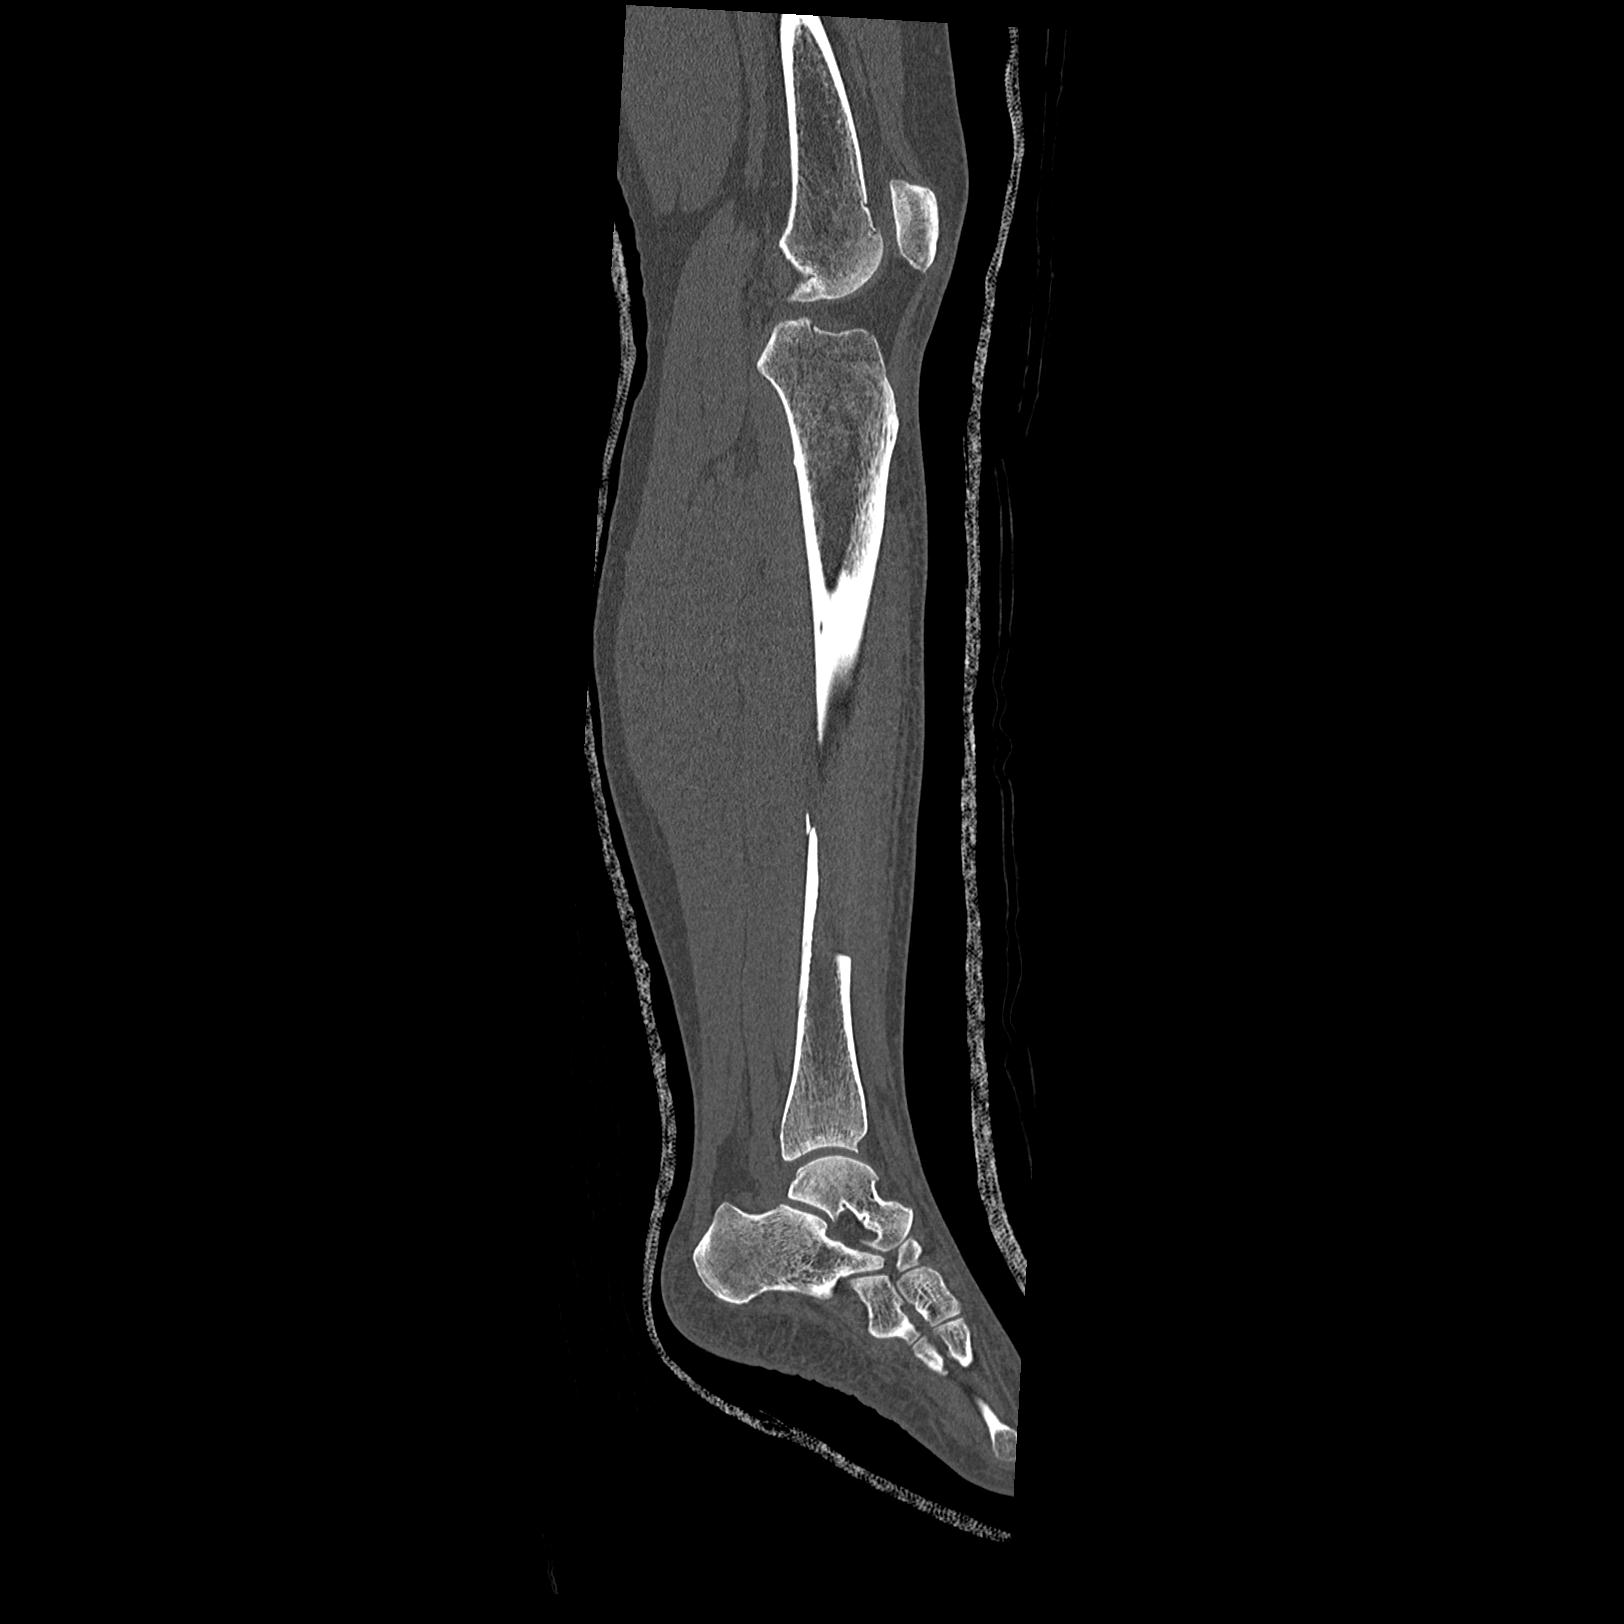

102803 1/12(キウスなし) 1/27 左下腿 4R 30歳女性 左脛骨軸内釘